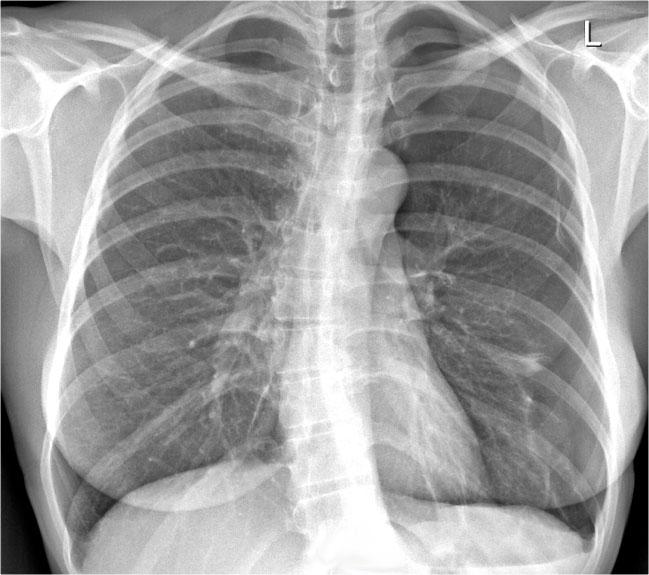

Ví dụ Lâm sàng: Dấu hiệu Kín đáo của Suy tim Sung huyết

Hãy bắt đầu bằng cách xem xét các phim X-quang ngực hiện tại.

Chỉ dựa trên các hình ảnh này, người đọc có thể nghi ngờ suy tim sung huyết (CHF), mặc dù các dấu hiệu còn khá kín đáo.

Bây giờ hãy xem lại phim cũ trước đó…

Việc cuộn qua lại giữa phim hiện tại và phim cũ giúp tăng đáng kể độ tin cậy trong chẩn đoán suy tim sung huyết.

Các dấu hiệu so sánh chính bao gồm:

- Kích thước tim: Tăng nhẹ so với phim trước; tuy nhiên, tim to đã hiện diện từ trước.

- Hệ mạch máu phổi: Cương tụ mạch máu nhẹ gợi ý tăng áp lực tĩnh mạch phổi.

- Hình ảnh mô kẽ: Dấu hiệu kín đáo của phù mô kẽ.

- Tràn dịch màng phổi: Tràn dịch lượng ít hai bên, với thay đổi kín đáo ở bờ dưới-sau của các thùy dưới, gợi ý tích tụ dịch.